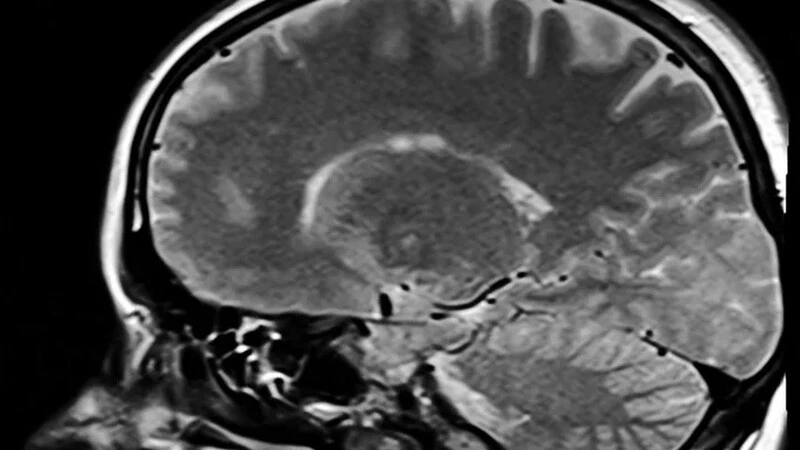

Восьмилетний Егор в этом году вместе со своими друзьями-сверстниками пошел в школу. Активный и улыбчивый, он даже не подозревал, что уже через несколько месяцев окажется на больничной койке. У мальчика начались проблемы со зрением, и родители принялись обследовать сына в областном центре. После очередного визита к специалисту их отправили на МРТ. Результат повергнул всех в шок.

— У Егорки нашли рак головного мозга и гидроцефалию. В голове у него собралась жидкость, состояние резко ухудшилось, поэтому было принято решение провести срочную операцию в областной детской больнице. Ему откачали жидкость. Это страшно. Вы представляете — здоровый, активный ребенок, и тут такое… Мы молимся каждую минуту. Надеемся только на лучшее. Нас поддерживают близкие, земляки. Спасибо всем огромное, — рассказала РИА «Сахалин-Курилы» мама мальчика Алеся.